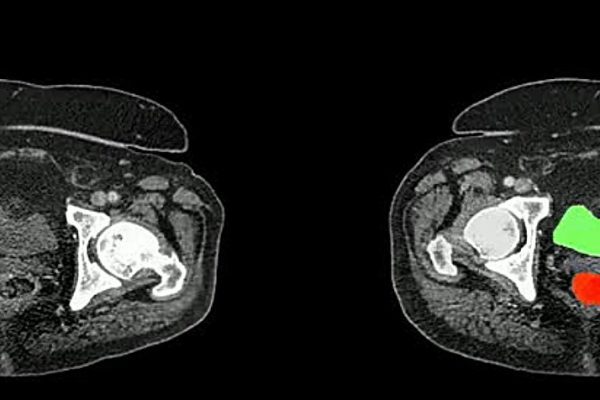

Un equipo internacional liderado por la Universidad Johns Hopkins ha desarrollado AbdomenAtlas, el conjunto de datos de tomografías computarizadas (TC) abdominales más grande hasta la fecha, que promete mejorar la detección temprana de cánceres abdominales. Radiologistas están comenzando a utilizar modelos de visión por computadora basados en inteligencia artificial (IA) para agilizar el laborioso proceso…